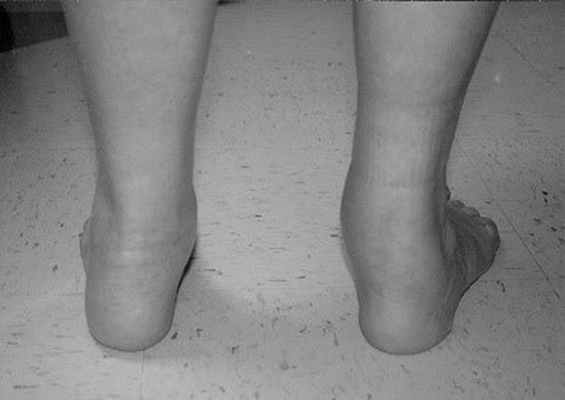

Определяется вальгусная деформация заднего отдела стопы – динамическое на 2 стадии, ригидное на 3-4.

На ранних стадиях отмечается отсутствие нормальное инверсии пяточной кости при вставании на мыски.

На 2 Б стадии присоединяется деформация переднего отдела стопы, он смещается кнаружи, приводя к появлению симптома названного «слишком много пальцев».

На этой стадии определяется недостаточное покрытие головки таранной кости ладьевидной костью, за счёт смещения первой кнутри. При этом определяется боль за верхушкой внутреней лодыжки. Начиная со второй стадии пациенты часто не могут выполнить тест подъёма на мысок одной ноги из-за боли в подтаранном синусе. Начиная с 3 стадии деформация стопы становится ригидной, то есть не исчезает и в отсутствие нагрузки.